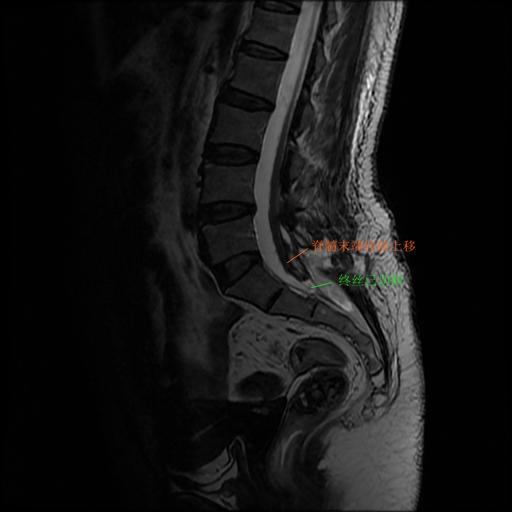

针对刘女士复杂病情,专家们决定采取脊髓拴系松解手术外加终丝离断手术治疗。在神经电生理监测下,术中在显微镜下仔细分离拴系区域两侧粘连,严密保护脊髓及神经,降低脊髓和神经的张力,切断粗大的终丝。手术后刘女士症状明显改善,对生活重燃希望。

术后MRI见终丝已离断,圆锥上移